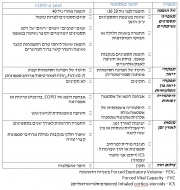

| 21:39, 5 במרץ 2015 | AsthmaCOPD4.jpg (קובץ) |  |

247 קילו־בייטים | Motyk | 1 | |